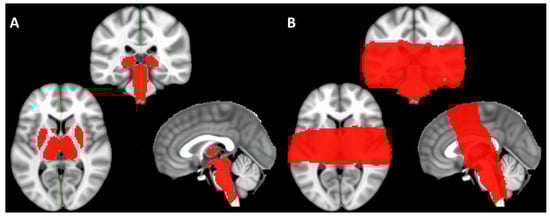

2. Materials and Methods